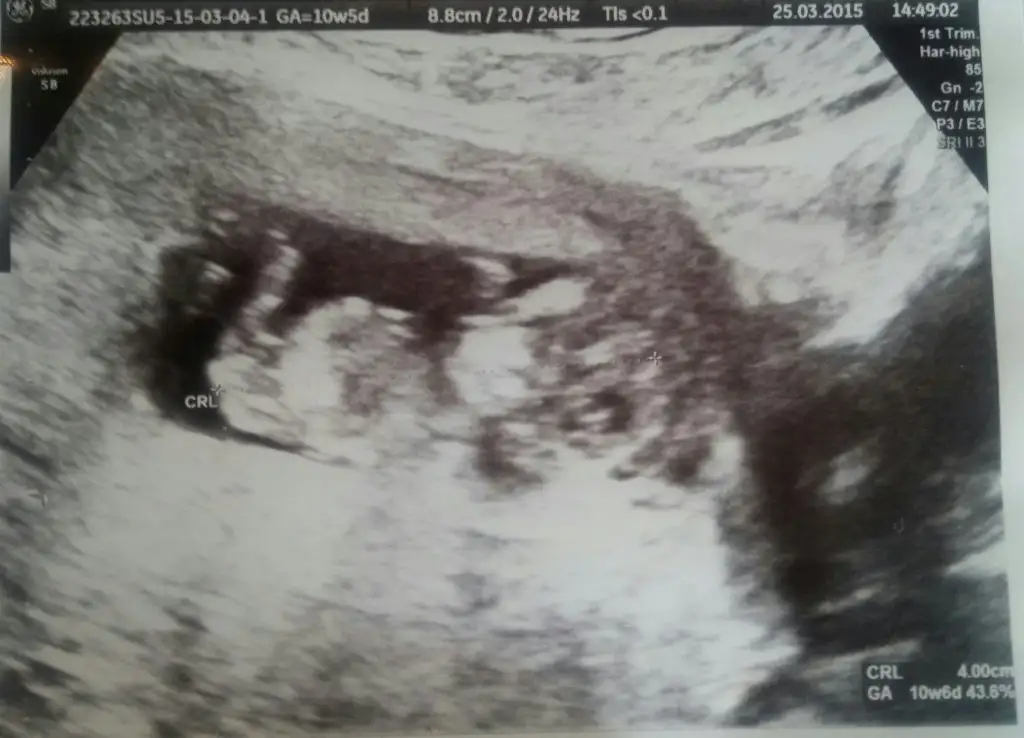

Kızlar ben de bugün ikili test için gittim. 4 gün önden gidiyoruz, 13+2'ymişiz :nazar::KK68: Doktor çok baktı bacak arasına bir şey söyledi ama kesin diyemeyiz dedi. Nub pek görünmüyor sanki, ben anlamadım. Bir de siz bakar mısınız, anlaşılıyor mu? Yoksa sonraki kontrol 4 hafta sonraaa :KK51: Allah'a şükür sağlıklı görünüyormuş ama.. bu da yeter tabii.. :KK68::nazar:

Bakın biri 10+6 fotosu biri 13+2. Dönmüş de minikim :KK46::confused:

• Bebişim 10+6.webp

Bebişim 10+6.webp

28,8 KB · Görüntüleme: 123

bu arada 10+6'dan bir şey anlamadım ama 12+5'deki görüntü erkek gibi gözüktü bana. ve bu haliyle bile pek şirin duruyor maşallah. Allah hayırlısıyla kavuştursun. :)

10+6'da kız diyen de oldu erkek de.. Bakalım şimdi tahminler ne olacak. Ben anlamadım pek :)